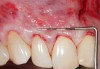

Fig 5. Preoperative. Class 2 Miller trauma-induced recession and associated tooth malposition.

Figure 5

Fig 6. Incision and flap relaxation. A vestibular incision subperiosteal technique-access incision (horizontal mucosal incision) allows for a full-thickness horizontal dissection. A total flap relaxation enables the clinician to avoid uncontrolled flap pressure on the APRF membranes and allows complete and passive coronal positioning of the soft tissues.

Figure 6